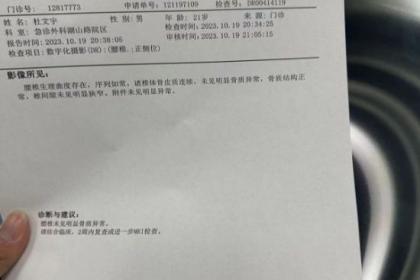

武汉惠鑫健康管理有限公司专业代开上海医院病历证明17267193882,诊断证明,医院病假条、病假单、请假条、病例单,医院休学证明、免军训证明、免体测证明,化验单、CT报告单、B超单、病理报告、心电图,三甲医院病例诊断证明、医院住院证明、医院出院证明,医院怀孕证明、结扎上环证明、流产引产证明,医院病危通知书、医院全套病历等等。长期与市区各大三甲医院保持良好关系,欢迎随时联系我们!

医院病假单主要就是由医生开取的一个关于身体的病状情况,在严重的情况下要请假休息才行。很多人在请假的时候不知道怎么开医院病假条,请直接联系我!只有写好医院请假条才能使自己在家里安心养病,休假也是为了自己的身体健康尽快恢复。医院一般不可以直接开病假条,但是经正规医院的医师检查后,可以为病人开具疾病诊断书、健康证明书等材料,而劳动者可以携带该材料去申请用人单位开病假条。

总之,现在很多情况都会要求开具各种各样的医院病历证明,譬如公司请病假,怀孕休假,学校办休学,免军训,免体免测等等。什么情况才能开具诊断证明?复杂也好,难办也好,放轻松一点,我们愿意为您代劳!